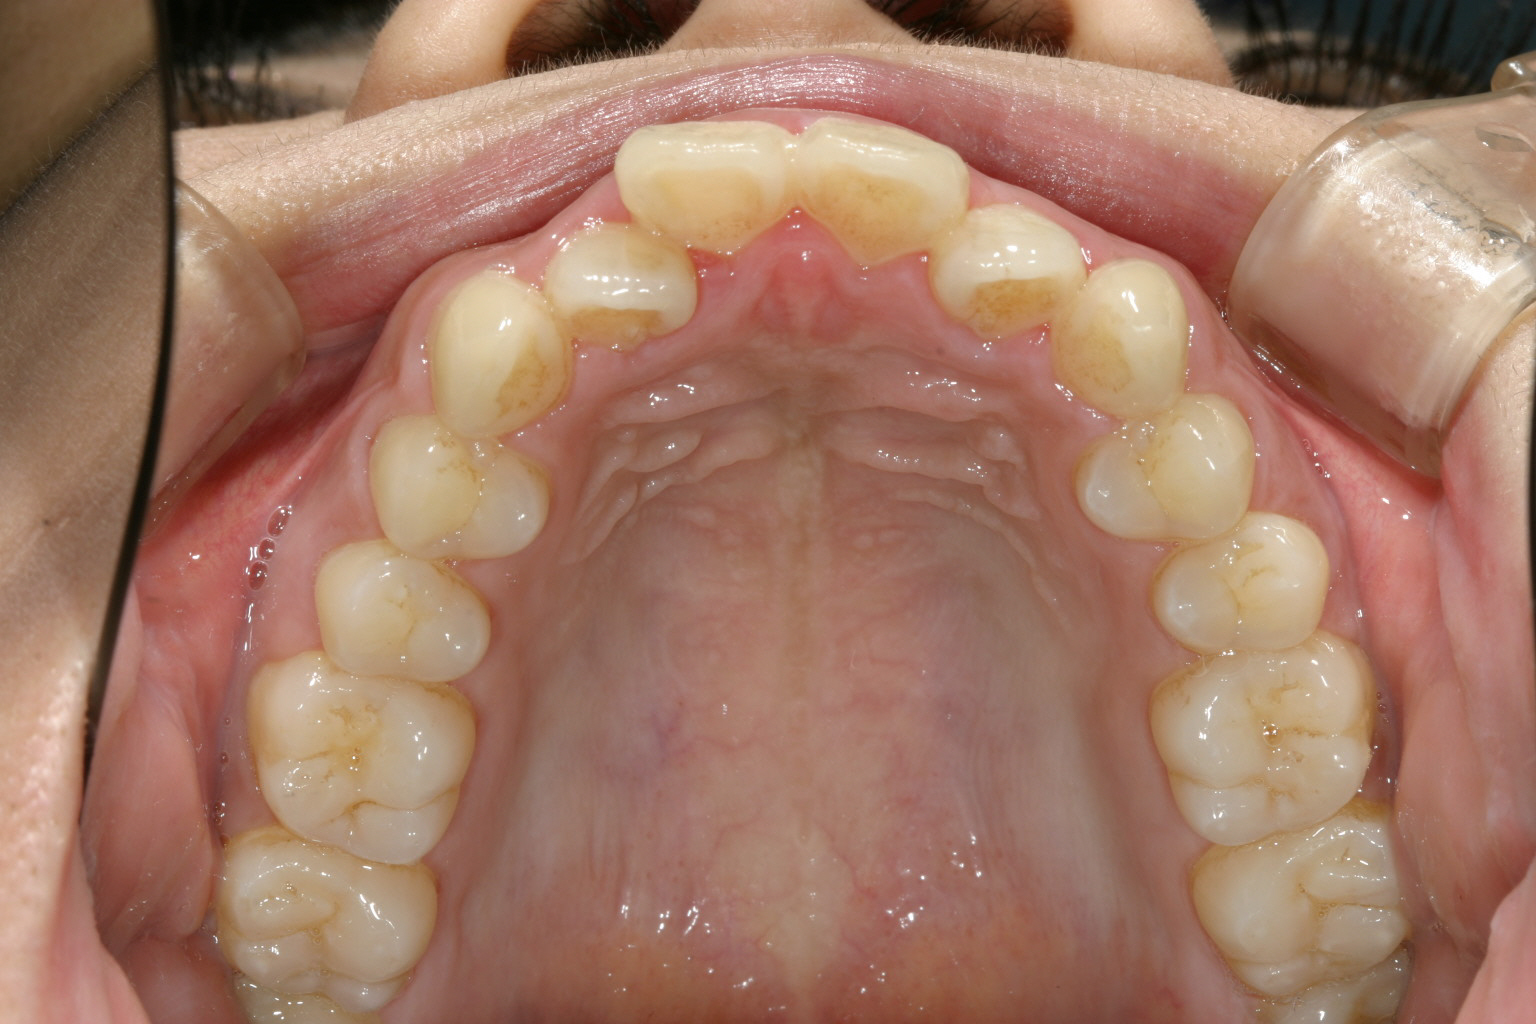

アーチがV字型で前歯が飛び出しています。

上顎は左右の小臼歯抜歯して出た前歯を引っ込めました。